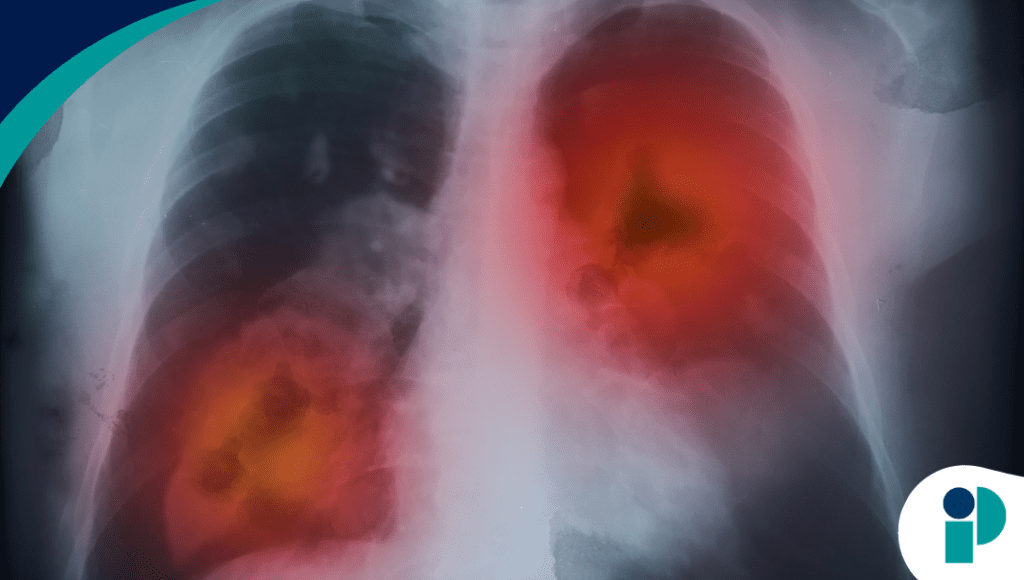

“Los resultados respaldan que la administración mensual mantiene eficacia y seguridad comparables al régimen más frecuente”, señala la información clínica revisada por la agencia reguladora. La Food and Drug Administration (FDA) aprobó un esquema de dosificación mensual para amivantamab coformulado con hialuronidasa-lpuj en combinación con lazertinib como tratamiento de primera línea en pacientes con cáncer de pulmón no microcítico avanzado con mutaciones EGFR.

El tratamiento se utiliza en combinación con lazertinib, un inhibidor de tirosina quinasa dirigido a mutaciones EGFR, consolidando una estrategia terapéutica dirigida en este subtipo molecular de cáncer de pulmón no microcítico. La integración de terapias biológicas y moleculares continúa redefiniendo el abordaje del NSCLC avanzado.